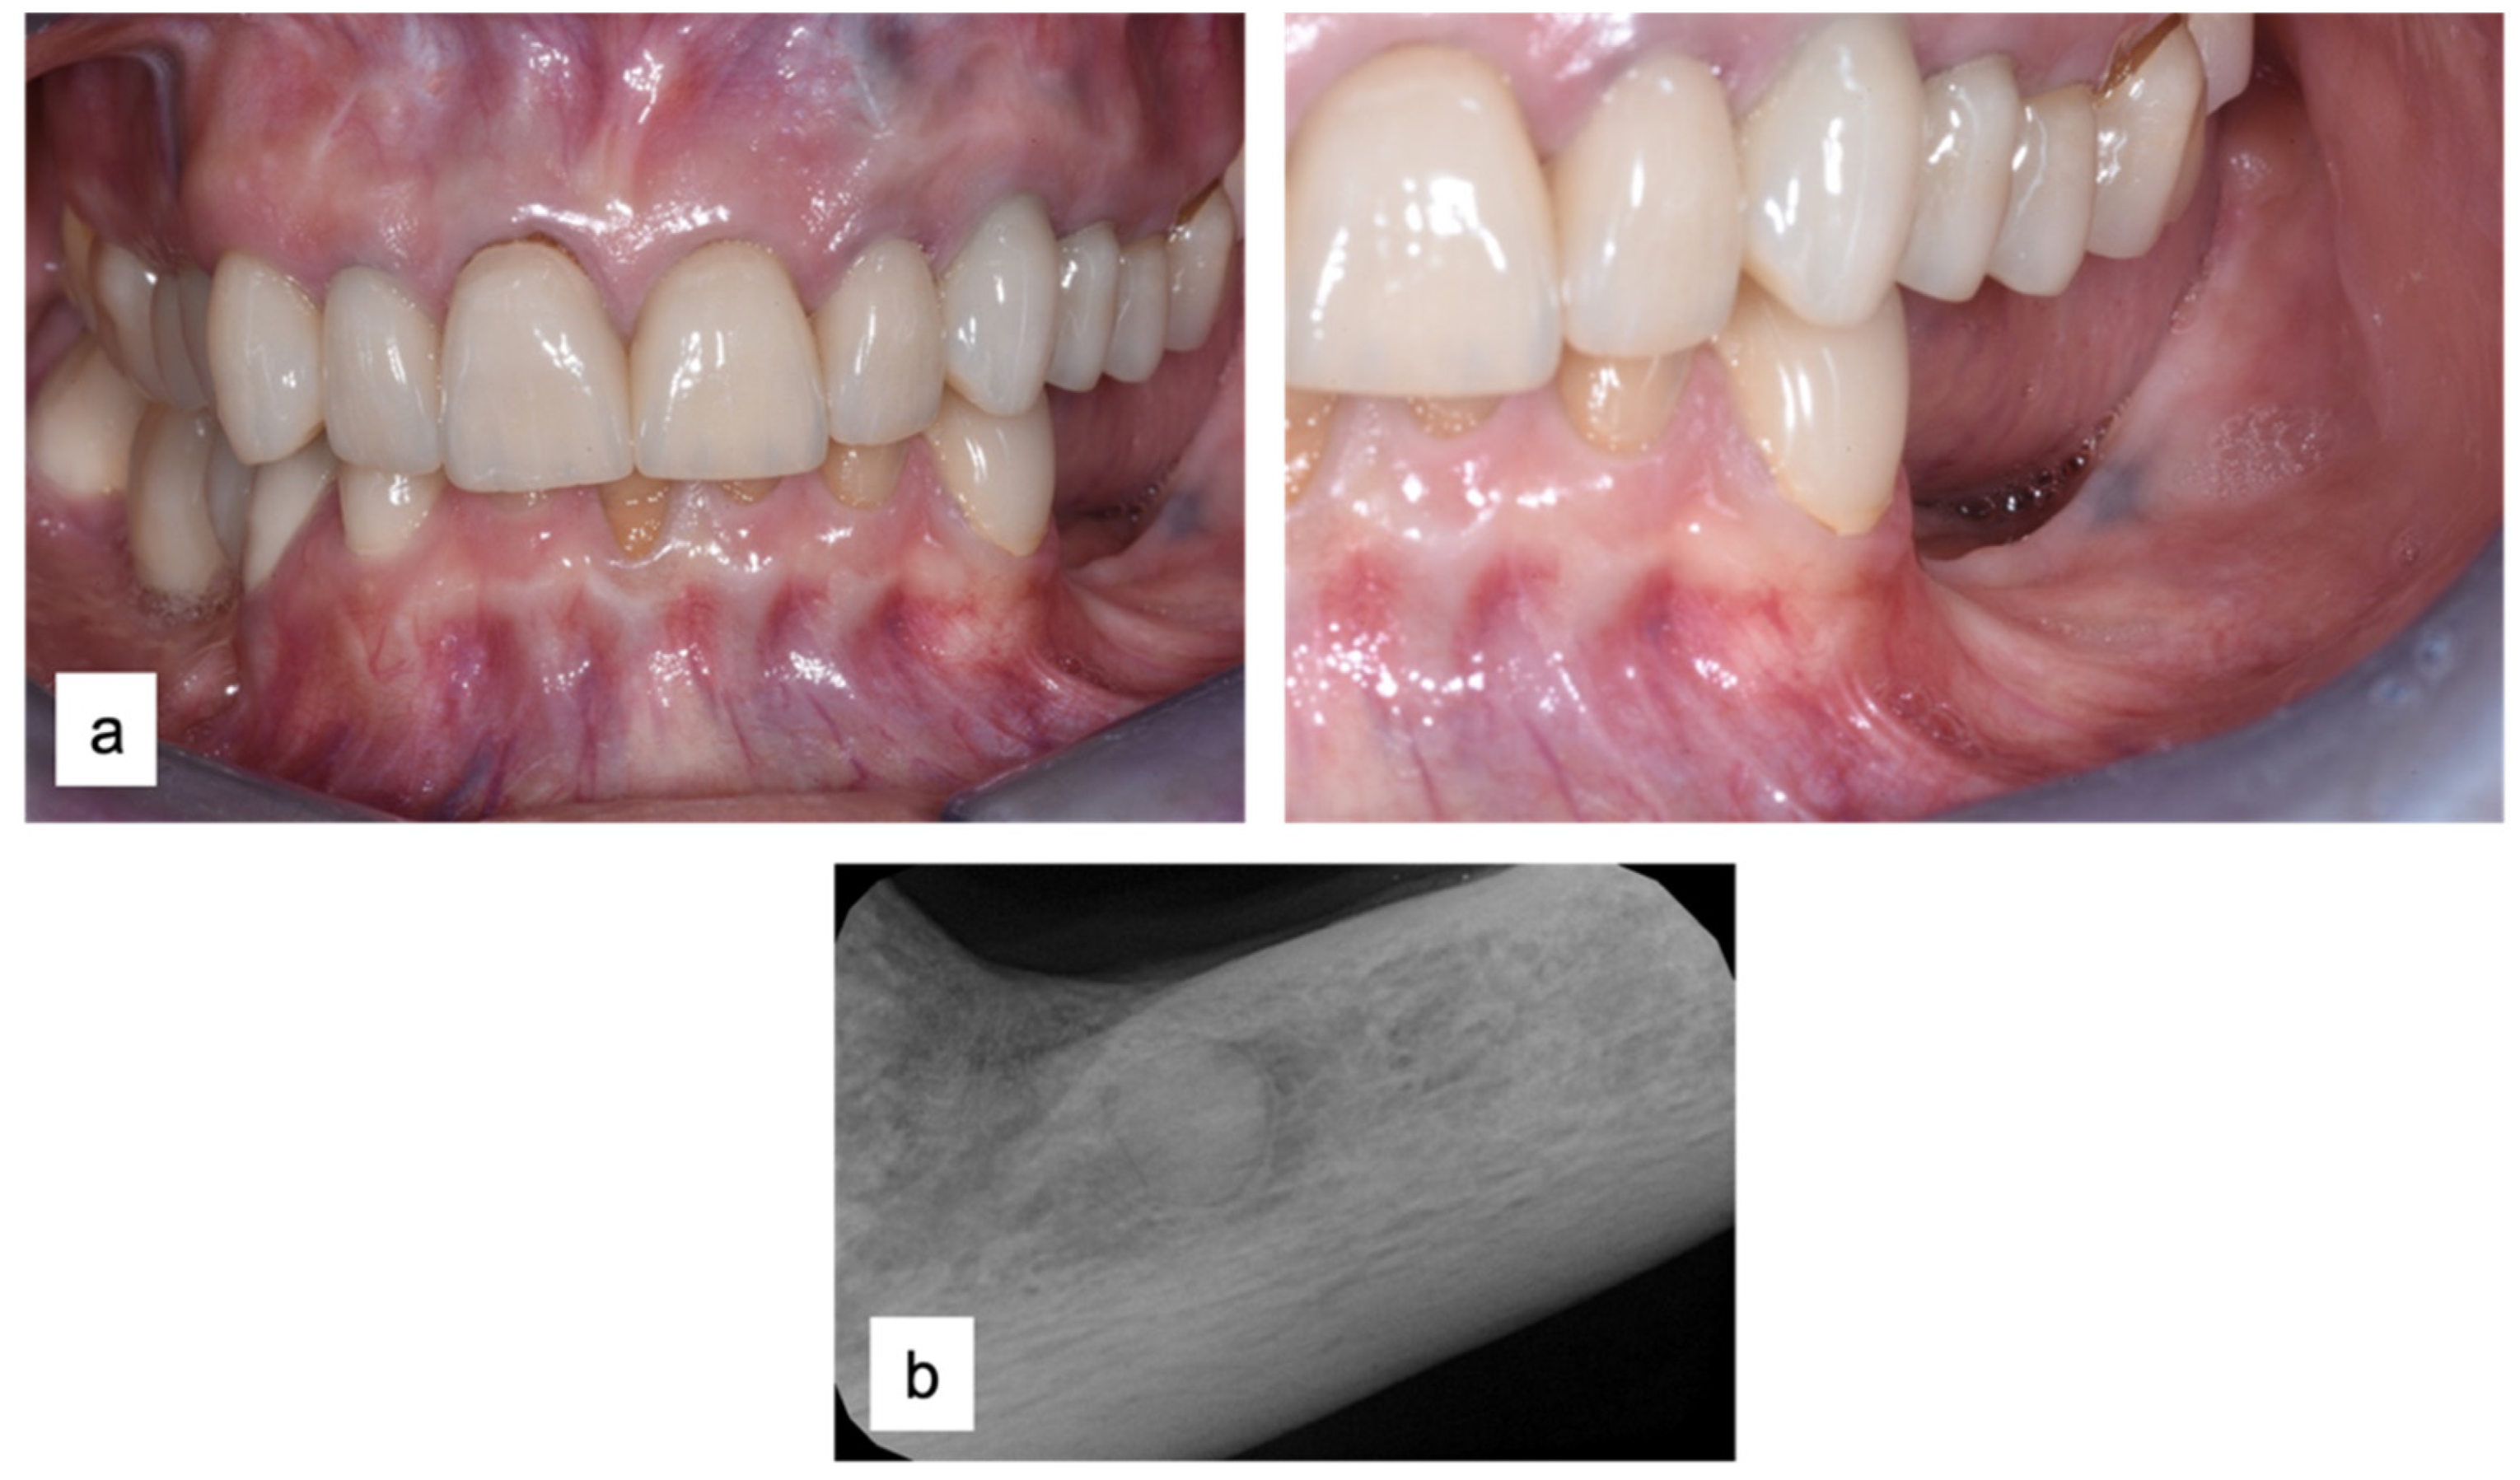

3.1. Clinical History

3.2. Soft Tissue Augmentation

| T0 | Initial Evaluation | Periapical status and CBCT Risk assessment Mucogingival evaluation |